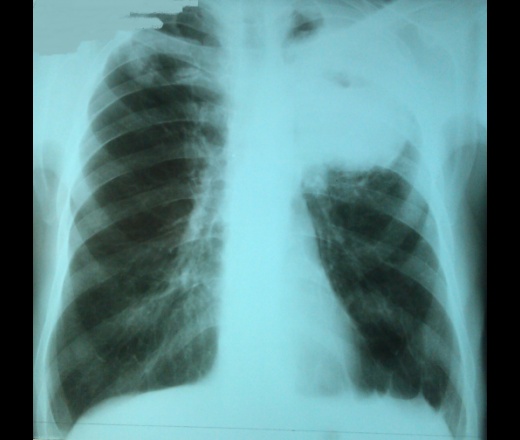

Мужчина, 65 лет. Все подробности (в т.ч. результаты анализов) пока неизвестны, R-картина довольно примечательная, поэтому делюсь. Конечно, уточню анамнез, выложу как только. Снимки с интервалом 20 дней.

При отсутствии полной информации, в диф. ряд посттуберкулезный фиброателектаз верхней доли левого легкого.

Если бы не плевро-диафрагмальные шварты слева и не "тенюха" на верхушке справа, то безусловно, на первом месте периферический (возможно кавитирующий) рак лёгкого.

Но учитывая "если бы не", на мой взгляд, линейная томография могла бы расставить все точки над "1"...

планировалась операция, из-за кардиальной патологии отложена на неопределенное время, высокая степень операционного риска;

клинический Ds: легочно-плевральная полость; выполнено дренирование полости, получен гной;

в 2016г. лечился по поводу пневмоторакса слева; R-архив не предоставил;

в архиве нашлась более ранняя КТ ОГК, опять только выборочные снимки, от 2016г., на тот момент в верхней доле полостному образованию не предшествовал ни инфильтрат, ни полость меньших размеров. Качество снимков оставляет желать... по возможности выложу;

Известно, что ранее была выполнена атипическая резекция верхней доли левого легкого (как давно - будем уточнять);

состоял на учете по поводу tbc, с учета несколько лет, как снят; в настоящее время исследование смывов из бронхов на МБТ и атипич.клетки отрицательны; анализы мокроты и плевральной жидкости на МБТ - отрицательны;

ФБС: дренажный гнойный бронхит с обеих сторон.

ОАК: повышены Lc до 8-10, СОЭ до 40-50.

при всем вышеизложенном рентгенологическое заключение: полостное образование верхней доли левого легкого